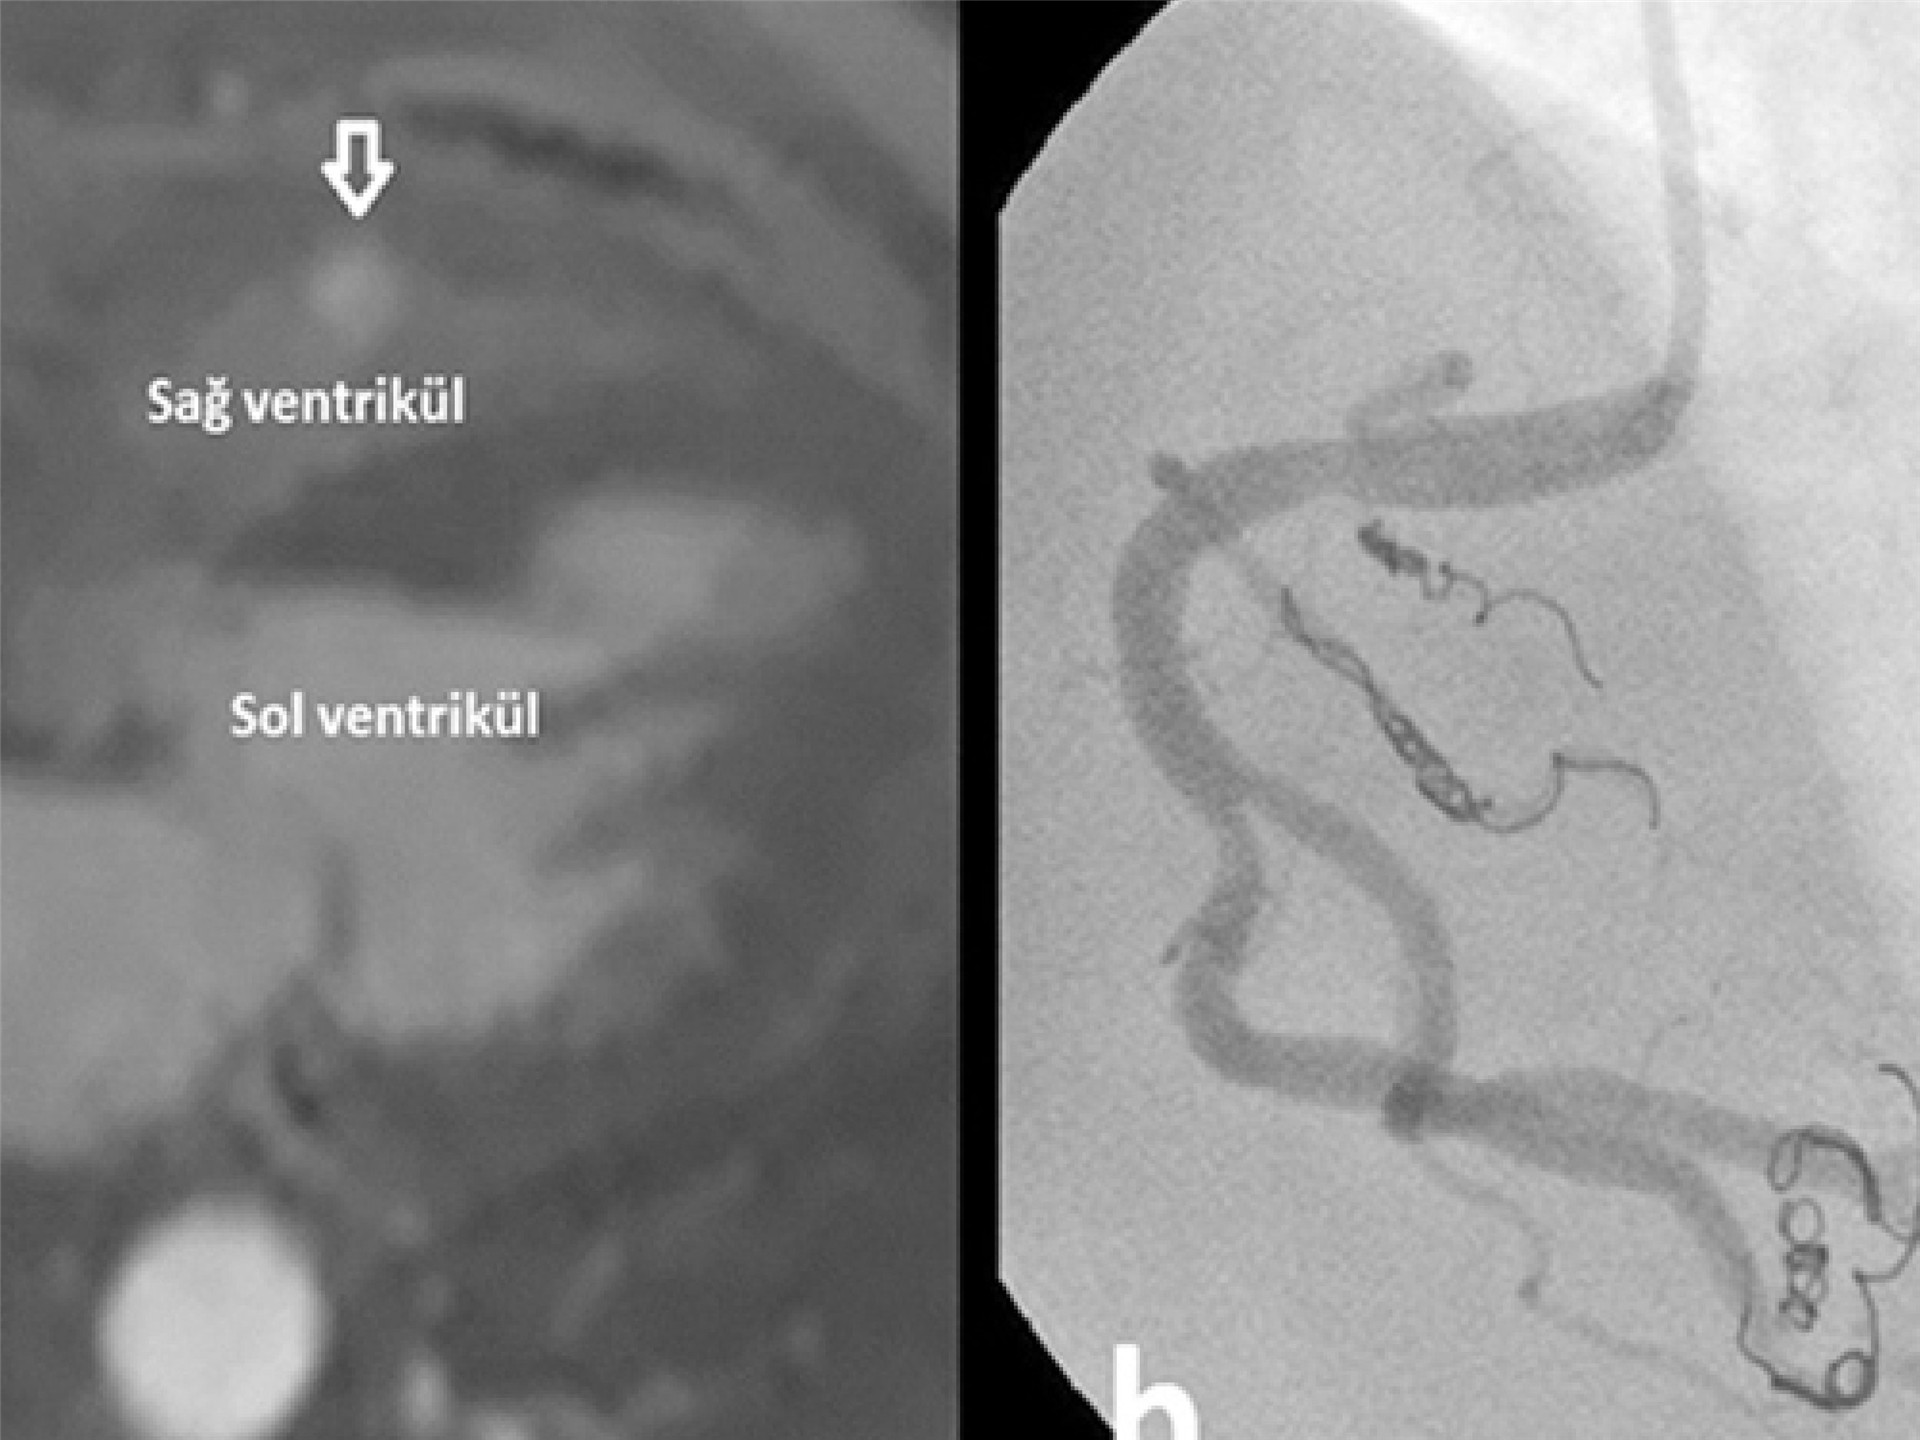

What Is Embolization Treatment?

Embolization is a minimally invasive treatment method designed to block abnormal blood flow or close abnormal vascular connections within a vessel. During the procedure, special catheters and embolic materials are used to seal the fistula or problematic vascular area.

This technique allows many vascular problems to be treated without the need for open surgical procedures.

• Microcatheter systems

• Embolic coil systems

• Vascular plug devices

• Specialized embolic materials

These technologies allow precise and controlled closure of the targeted vascular area.